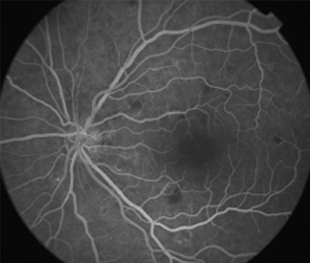

Angiografía OI

- Angiografía: teñido arterial, escape capilar, más tardíamente, no perfusion arteriolar y venular con teñido de las paredes vasculares y dilatación venosa.